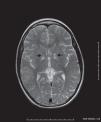

Hallazgos radiológicosEn la resonancia magnética (RM) craneocervical se aprecia hiperintensidad de la señal, en secuencias potenciadas en T2, más llamativa en núcleos pálidos (flechas en fig. 1) y, en menor medida, en mesencéfalo (punta de flecha en fig. 2), sustancia negra y tubérculos cuadrigéminos, con restricción de la difusión (flechas en fig. 3), así como en la región periependimaria de la médula espinal a nivel de C2-C4 (flecha en fig. 2) con discreta atrofia cerebral y cerebelar.

Histopatologicamente es una enfermedad que se caracteriza por la degeneración espongiforme (vacuolización) del tejido nervioso, y sus hallazgos radiológicos más frecuentes en RM son la atrofia cerebral y cerebelar (presentes en nuestro caso), con lesiones hiperintensas bilaterales, en la sustancia blanca subcortical periférica, fibras en U, sustancia negra, globos pálidos y tronco del encéfalo (estas dos últimas localizaciones son las afectadas en el caso presentado figs. 1 y 2). La sustancia blanca subcortical suele ser anormal. Es característico observar restricción de la difusión (hiperintensidad de la señal en la secuencia potenciada en difusión) de la sustancia blanca afectada2–4 (objetivado en nuestro caso fig. 3).